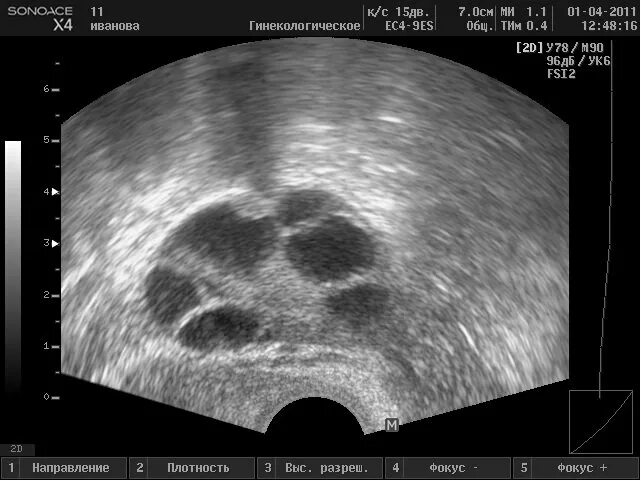

5 6 фолликулов в яичнике